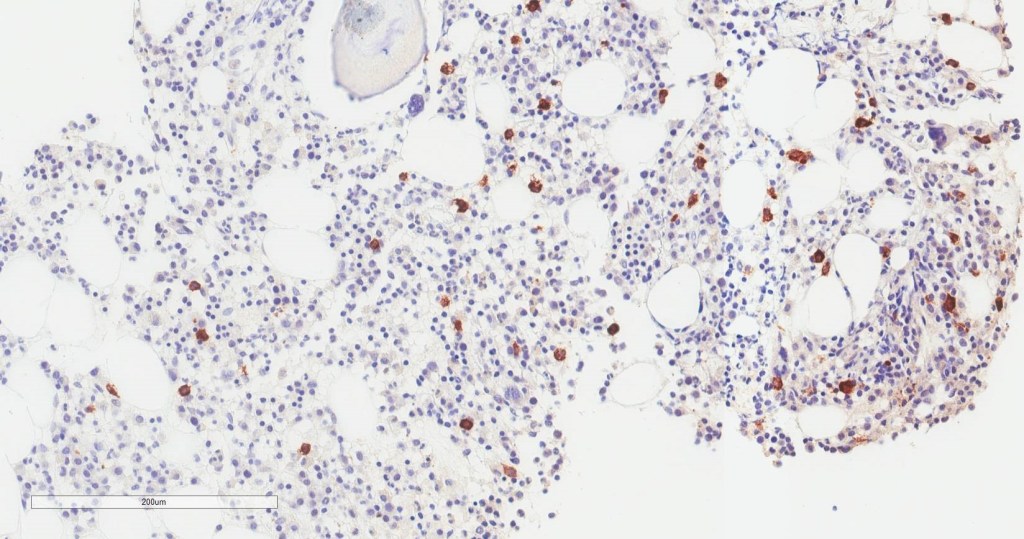

If you read my last blog, you heard the about the story “if You Give a Mouse a Cookie” by Laura Numeroff.4 The curious little mouse has a mind that never rests. As his mind wanders and hops from one thing to another, he keeps discovering more things to check out along the way. Medical laboratory lcientists are a lot like this. We’re a curious bunch, and, in investigations, one thing often leads to the next. Well folks, the mouse has struck again! We were given another cookie in the form of these beautiful cells.

These cells were found by my coworker Liz Marr, MLS(ASCP), and the adventure began! First, we wanted to know what those were, and then we needed to find out more about them, and then, mostly, I wanted to know why in almost 40 years of working in and teaching hematology that I have never before seen this!

The story begins with our case history. We received a CBC from a 71 year old female with a 4 year history of untreated chronic lymphocytic leukemia/ small lymphocytic lymphoma(CLL/SLL). The patient’s recent history included a myocardial infarction(MI) 5 months prior. The patient was found to have leukocytosis (WBC 25.38 x 103/μL) and absolute lymphocytosis (18.25 x 103/μL) with normal hemoglobin and hematocrit (Hgb 13.4 g/dL, Hct 40.8%) and normal platelet count (272 x 103/μL). The differential had 71.9% lymphocytes with many abnormal forms noted. The slide was sent for a pathology review. The pathologist reported “Atypical lymphocytosis consistent with patient’s known chronic lymphocytic leukemia/small lymphocytic lymphoma (CLL/SLL) Filament-like inclusions are present in the cytoplasm which has been previously reported in patients with CLL.”

A literature search revealed only a few articles about intracytoplasmic inclusions in CLL. Cytoplasmic inclusions in lymphomas are uncommon, but have been noted as vacuoles, crystals, and pseudocrystals. These crystalline inclusions represent immunoglobulin(Ig) heavy and light chain that precipitate in the cytoplasm. Using electron microscopy it has been found that theses Ig deposits localize in the rough endoplasmic reticulum (RER).5 When surface Ig can be demonstrated on the B lymphocytes, it has been found to be same as Ig in the inclusions.6

In two published studies that describe these crystal like inclusions, photographs are very similar to the ones we found on our patient.3,5 It is interesting to note that, in these two studies, neither of the subjects was a known CLL patient. The inclusions were noted in the patients’ cells and the peripheral blood was subsequently sent for flow. Phenotypes reported confirmed monoclonal B-cells representing a large percentage of cells. Huang reported monoclonal B-cells which expressed CD45, CD19, CD20, CD22, CD79b, CD5, CD23, CD148 and CD200(hi), with partial expression lambda, and negative for FMC7, CD10, CD11c, CD49d, CD103, CD38, CD25, CD160, IgM, CD81, kappa and Ki67.3 In the Ramlal case study, phenotype was CD5, CD19, CD20, CD23, positive, CD10, FMC7 negative.5 On the basis of flow, along with the CBC results, the patients were diagnosed with CLL.

Our case study patient and the various reports found in literature had common flow cytometry immunophenotypes. Patients were all either previously diagnosed with CLL or lymphocytic lymphoma, or were diagnosed at the time of the findings of these inclusions. While these crystalline inclusions alone are not considered diagnostic for CLL, their recognition can be used to assist in a prompt diagnosis of a lymphoproliferative disease. And they are so pretty! What medical laboratory scientist doesn’t love pretty cells? Be like that mouse. Be curious, keep your eyes open, and be on the lookout for these interesting cells in CLL patients, but, more importantly, in patients with lymphocytosis without a known diagnosis of a lymphoproliferative disorder.